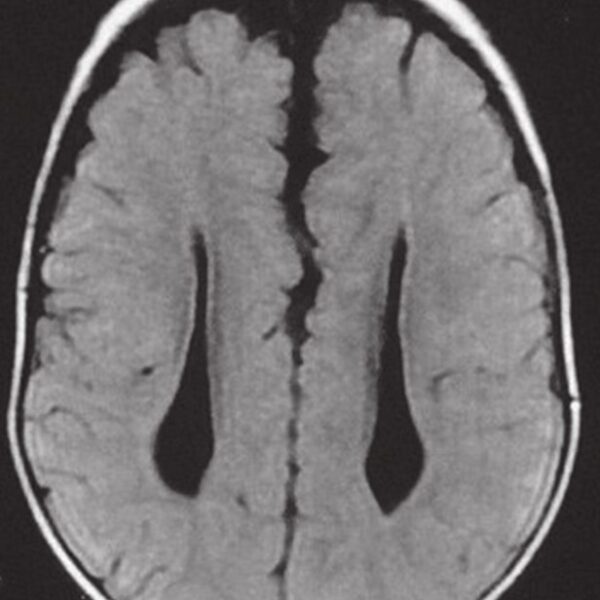

MRI

Showing 1–9 of 86 results